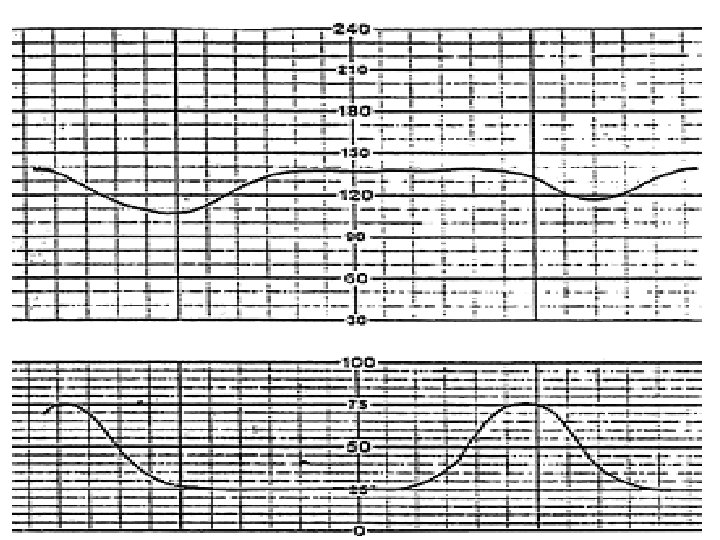

Sinusoidal and Pseudosinusoidal Patterns Sinusoidal pattern: A smooth, undulating pattern, lasting at least 10 minutes with a fixed period of three to five cycles per minute and an amplitude of 5 -15 bpm. Pseudosinusoidal: Usually caused by drugs such as Nubain or Stadol.